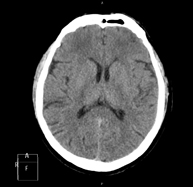

Skull CT

Radiological test that provides high definition anatomical images of the skull (brain stem, cerebellum, cerebrum, cranial calotte, etc.) using CT (Computed Tomography) equipment. Indicated for: trauma, headache, memory disorders, sudden loss of strength in a limb or half of the body.